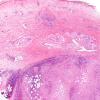

Lymphomatoid Granulomatosis (4)